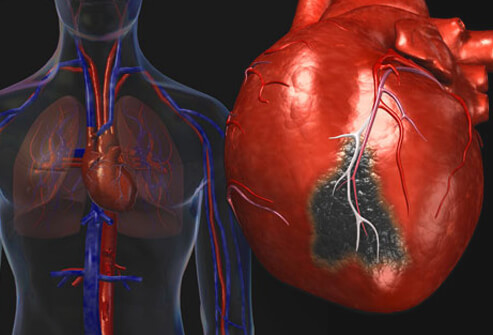

Pe masura ce oamenii imbatranesc, odata cu ei imbatraneste si inima si din cauza fragilitatii sale riscul de a suferi de o boala cardiovasculara creste considerabil. Toata lumea poate reduce acest risc la minim, daca se hranetse corespunzator si are grija sa duca o viata sanatoasa si echilibrata. Insa, romanii nu iau masuri, ori sunt ignoranti ori pur si simplu se lasa in mana destinului, repetandu-si in gand „Ce-o fi, o fi!”. In Romania peste 60% din decese apar din cauza bolilor cardiovasculare, ceea ce ne plaseaza pe primul loc in Europa atat in privinta mortalitatii cat si a numarului de imbolnaviri. Bolile vasculare survin pe fondul unui stil de viata nesanatos si dezordonat, din cauza fumatului, sedentarismului si stresului cauzat de factori externi, dar mai ales din netratarea altor afectiuni asociate bolilor de inima si anume obezitatea, hipertensiunea si altele. Dar mai exista si alti factori independenti de noi precum ereditatea, varsta sau sexul. In prezent din ce in ce mai multe femei sunt afectate de acest tip de boli, cu toate ca in trecut barbatii erau cei ce ocupat loc fruntas. De asemena varsta de aparitie a bolilor vasculare scade considerabil odata cu trecerea timpului.